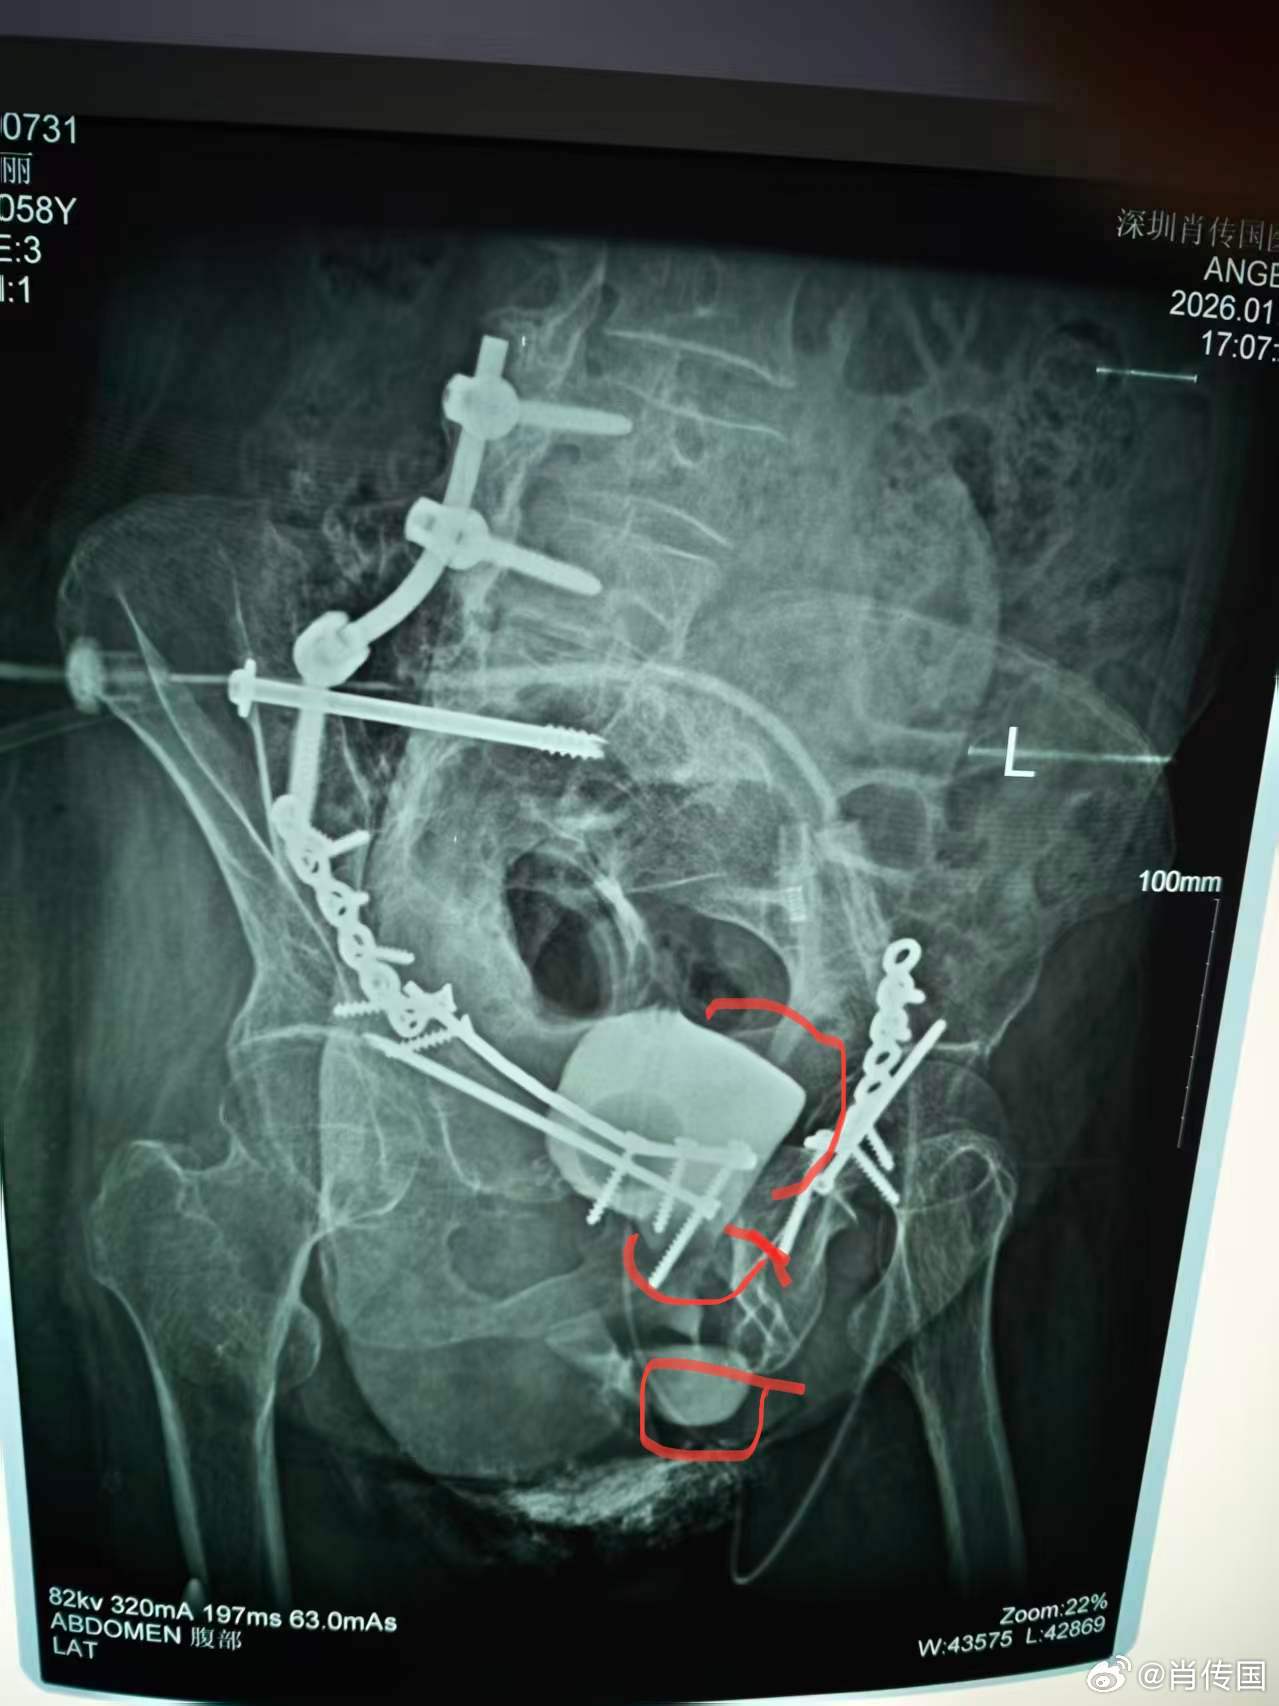

我因肖氏反射弧神经泌尿外科出名,但我的专业实际是整形泌尿外科,作为美国泌尿外科学会Fellow,在最有名的美国泌外整形专科学习工作了二年,回国后除了男女变性没法作,作了无数极端困难泌尿生殖系整形手术,下面这例的复杂困难程度可进入前五吧:介绍一例某省级医院转诊的少见的复杂膀胱瘘,主要给医学同行们参考。7年前因车祸骨盆严重多发骨折,请上海某知名医院骨科专家急会诊手术内固定骨盆。因出血严重,骨盆固定耗时甚长,故仅上尿管未探查处理膀胱等盆腔器官。术后数月出现左腹股沟和会阴部直肠皮肤瘘(耻骨骨拆刺破所致),在外院修复成功。后又发现右会阴大阴唇中上段外侧尿瘘。在外院曾试行经膀胱会阴瘘修补,太过复杂而放弃,转来我院。 经二次手术,治愈。